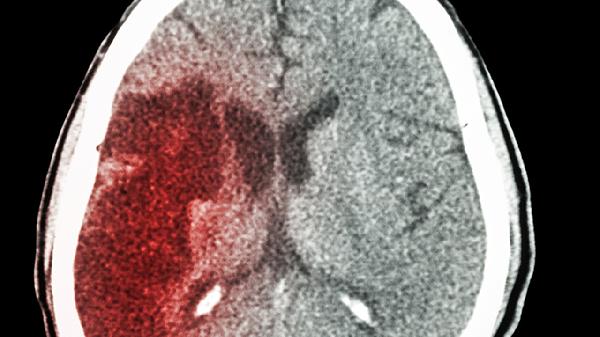

颅底骨折或垂体卒中可直接破坏垂体结构,引起急性激素分泌紊乱。典型症状包括突发头痛、视力下降伴肾上腺皮质功能不全。紧急处理需静脉注射糖皮质激素,后期根据损伤程度进行长期激素补充治疗。